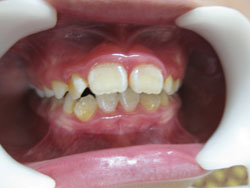

- *Răng mọc chen chúc:

- Răng mọc chen chúc là tình trạng các răng sắp xếp lộn xộn, không ngay ngắn trên cung hàm , răng mọc không đều, các răng khấp khểnh do thiếu chỗ (răng quá to hay xương hàm cung răng quá nhỏ không đủ chỗ để các răng sắp xếp).